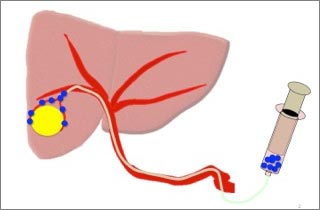

図2

腫瘍に栄養を送る動脈までカテーテルを進めて、血管を詰める粒(塞栓物質)を注入します。

抗がん剤を流すこともあります。